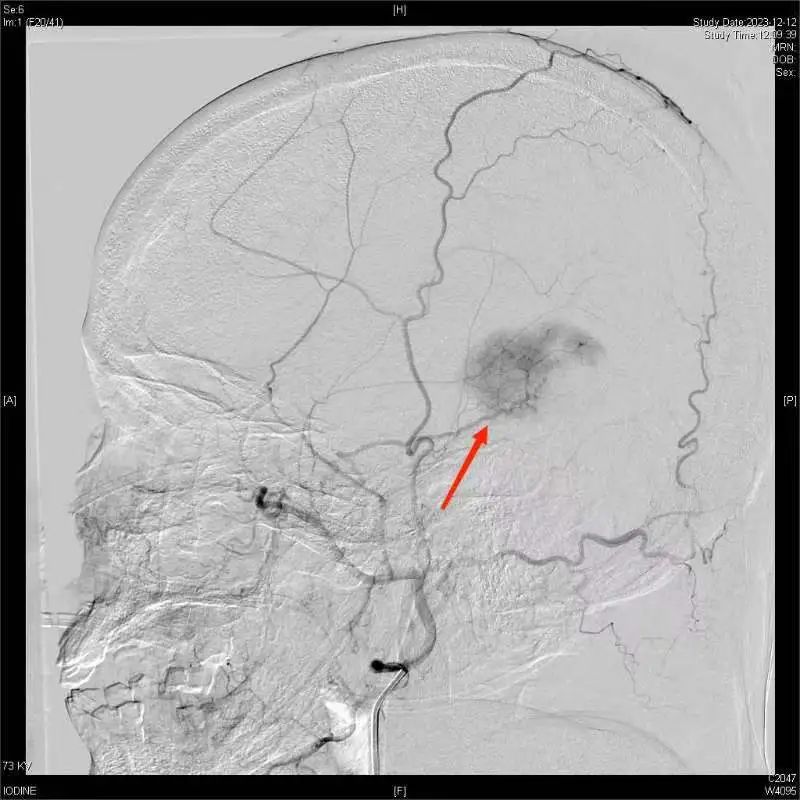

术前通过介入找到肿瘤供血动脉,精准栓塞

为了确保手术成功,神经外科术前与麻醉科、导管室等相关科室进行充分沟通,做好麻醉、备血等手术准备。首先进行全脑血管造影术,吴世忠副主任医师术中顺利找到肿瘤主要供血动脉颌内动脉分支,成功栓塞,阻断肿瘤80%的供血。第二天马上进行全麻下开颅肿瘤切除术,在魏德主任医师、郑诗豪副主任医师、蔡振俊医师的共同努力下,历时5小时就成功全切肿瘤。术后麻醉清醒患者即语言流利、神志清醒,肢体活动正常,目前已康复出院。